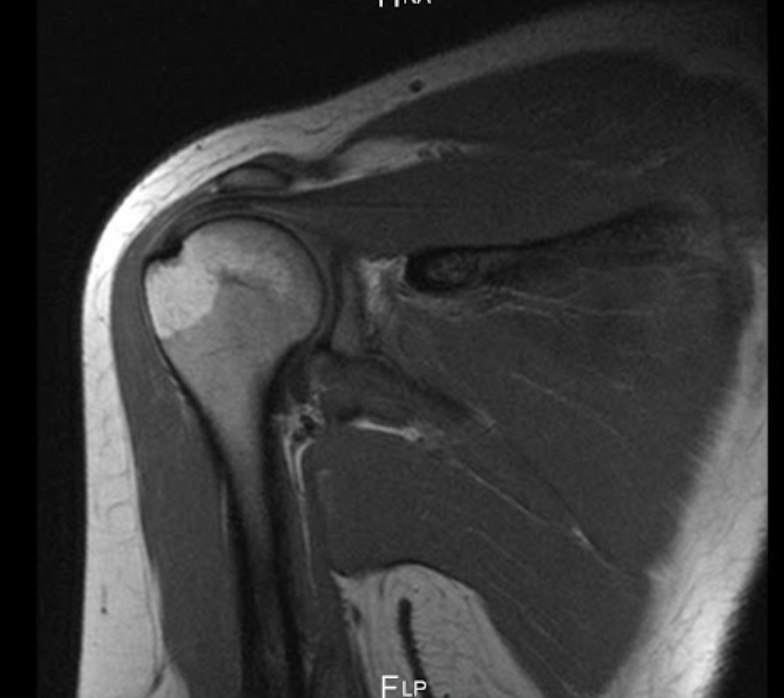

A

Rotura tendon supraespinoso